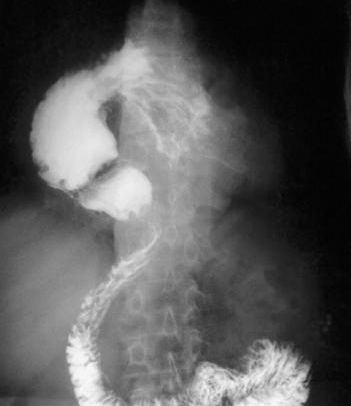

Diaphragmatic hernia before and after reduction of the stomach (Courtesy Dr. V. Penopoulos)

Water-soluble gastrografin meal showing postoperative normal positioning of stomach (Courtesy Dr. V. Penopoulos)